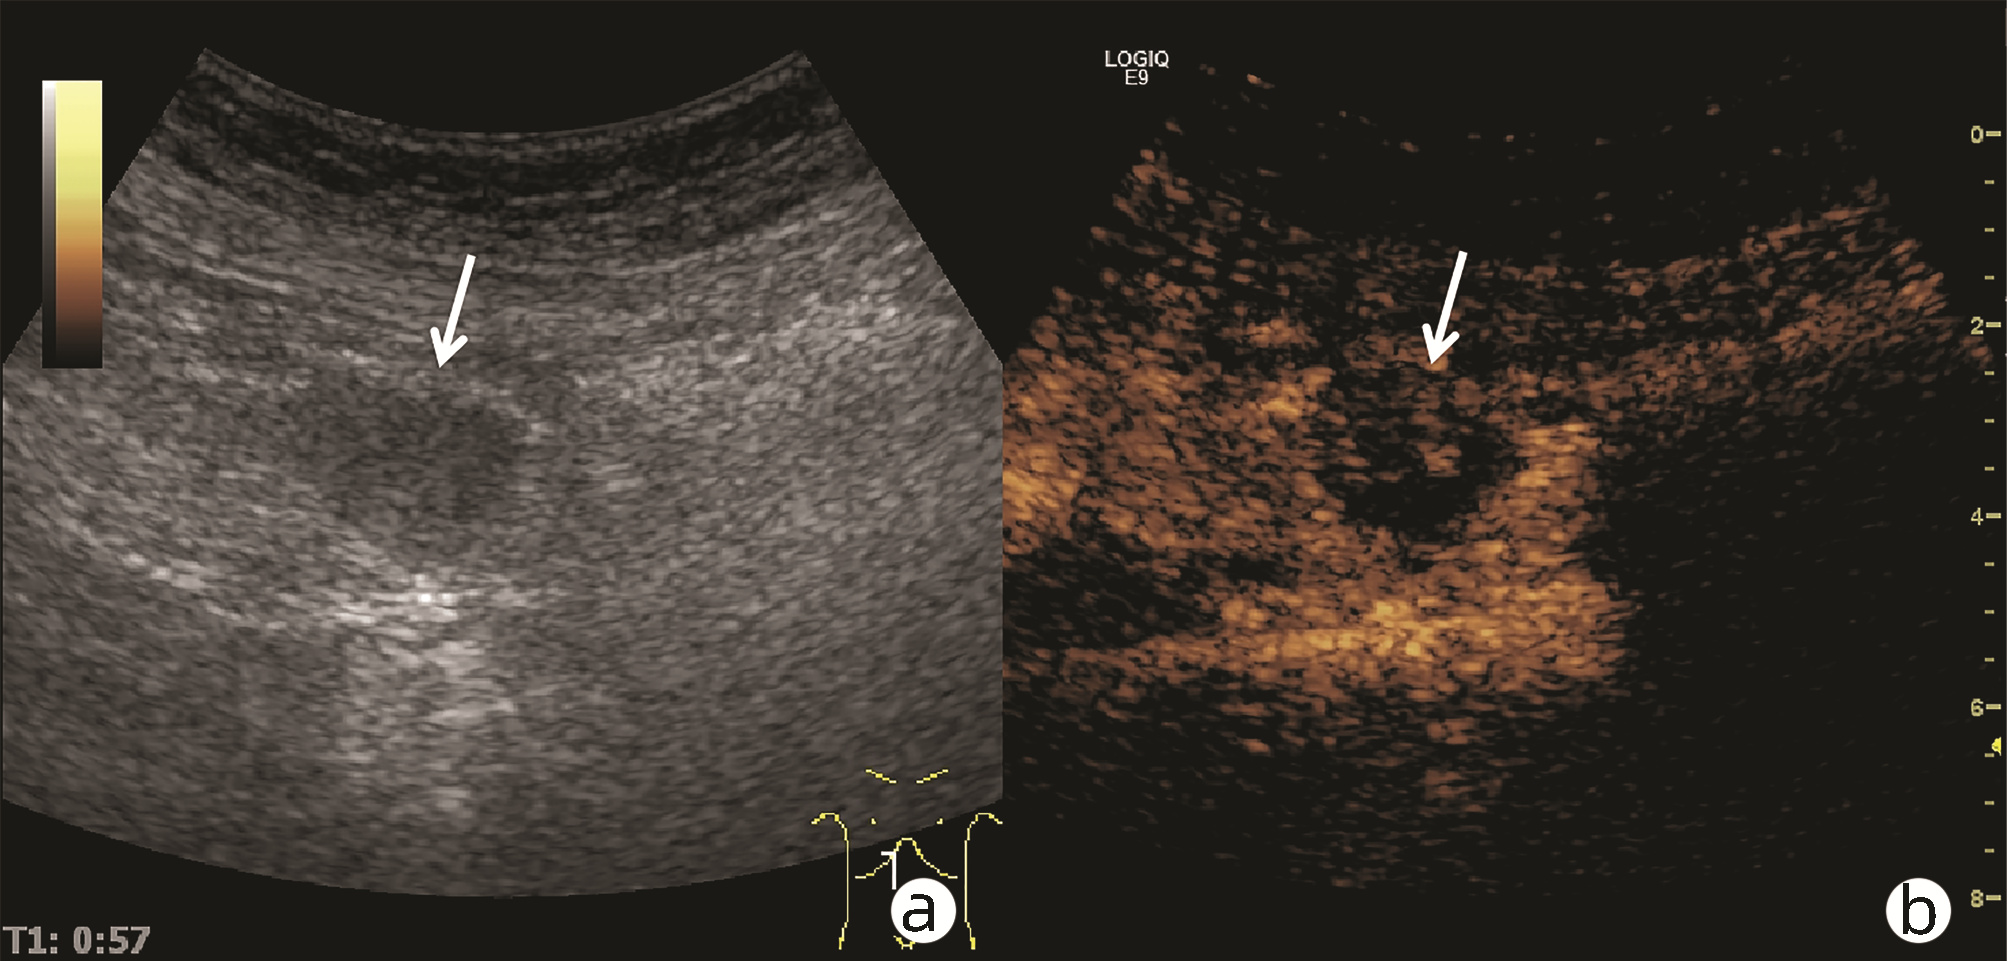

Ultrasound findings and contrast-enhanced ultrasound findings of mass-type autoimmune pancreatitis versus pancreatic ductal adenocarcinoma

Xiangliu OUYANG, Yunxia HAN, Lichun ZHENG, Yingchun ZHAO, Xinyu SHEN, Wenjun ZHANG, Yanbin WANG

2022, 38(6): 1351-1355. DOI: 10.3969/j.issn.1001-5256.2022.06.025

Abstract(1465) HTML (554) PDF (3738KB)(58)

Abstract:

Objective  To investigate the value of ultrasound and contrast-enhanced ultrasound (CEUS) in the differential diagnosis of mass-type autoimmune pancreatitis (AIP) and pancreatic ductal adenocarcinoma (PDAC).  Methods  A retrospective analysis was performed for the clinical data, ultrasound findings, and CEUS findings of 11 patients with mass-type AIP who were diagnosed in Tangshan Workers' Hospital from January 2015 to December 2020, and their characteristic manifestations were analyzed and compared with the data of 23 patients with PDCA. The chi-square test was used for comparison of categorical data between two groups.  Results  For the 11 patients with mass-type AIP, CEUS had a diagnostic accuracy of 63.64%, and all of these patients had hypoechoic single lesions; the patients with clear boundaries, regular morphology, pancreatic duct dilatation or cutoff, and blood flow signal accounted for 54.55%, 63.64%, 18.18%, and 36.36%, respectively, while in the PDCA group, such patients accounted for 30.43%, 34.78%, 78.26%, and 21.74%, respectively, and there was a significant difference in the presence or absence of pancreatic duct dilatation or cutoff between the two groups(χ2=11.089, P < 0.05), with no significant differences in the other indices (all P > 0.05). For the 11 patients with mass-type AIP, CEUS showed that 7 patients (63.64%) had hyperenhancement and 4 (36.36%) had iso-enhancement in the arterial phase, and 5 patients (45.45%) had hyperenhancement in the arterial phase and 6 (54.55%) had iso-enhancement in the venous phase; for the 23 patients with PDCA, 22 (95.65%) had hypoenhancement of lesions in both arterial and venous phases, and there were significant differences in the enhancement pattern in arterial and venous phases between the two groups (χ2=30.345 and 30.084, both P < 0.05).  Conclusion  The enhancement pattern of CEUS and the presence or absence of pancreatic duct dilatation or cutoff have a relatively high value in the differential diagnosis of mass-type AIP and PDCA.